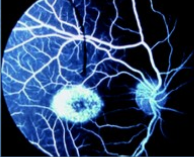

Valoración del escotoma en pacientes con enfermedad de Stargardt